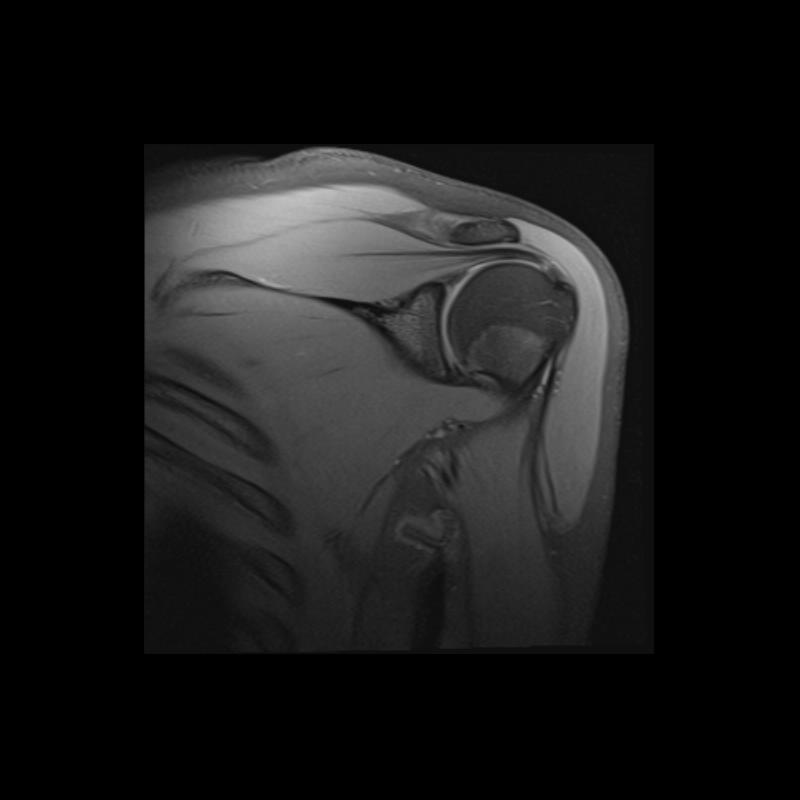

Shoulder MRI Anatomy